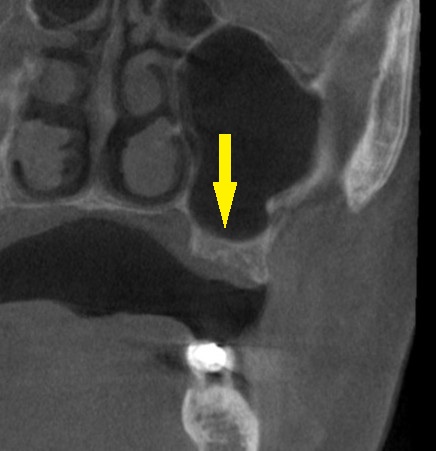

レントゲン、CTを撮影すると、骨幅は十分ですが、高さが3~4mmと、通常のインプラント埋入を行なうには、かなり不足でした。

何らかの骨造成が必要なのですが、年齢も考えて、あまり大変なことはしたくないとのご希望でしたので、人工骨を補填しての骨造成は行わず、ワイドショートインプラントで対応させていただくこととしました。

本日、左第一大臼歯に直径6.0mm長さ7mm、第二大臼歯部位に直径5.0mm長さ7mm、のインプラント埋入術を施行しました。

下の写真が手術前後のCTです。